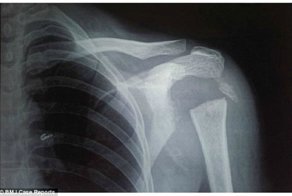

А вот у гонщика Дэвида Перли сердце останавливалось 6 раз. После того, как на гонках в 1977 году ему пришлось резко затормозить и на протяжении всего 66см. снизить скорость со 173 км в час до нуля. Из-за огромной перегрузки он получил 3 вывиха и 29 переломов.